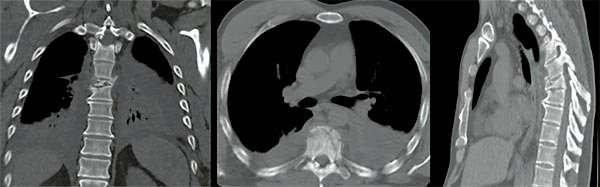

Figura 4:

Caso 8. Hombre de 52 años, accidente vehicular de alta energía cinética. Fractura cerrada de antebrazo, síndrome de distrés respiratorio, hemotórax bilateral, hematocrito en descenso. Se diagnostico una fractura A4 de T8 con mínimo compromiso del canal espinal, posición en cifosis y hemotórax bilateral a predominio izquierdo.

Figura 5:

Caso 8. Se realizó una estabilización percutánea T6-T10. El paciente retornó a UTI, para estabilizar su cuadro respiratorio y hemodinámico.